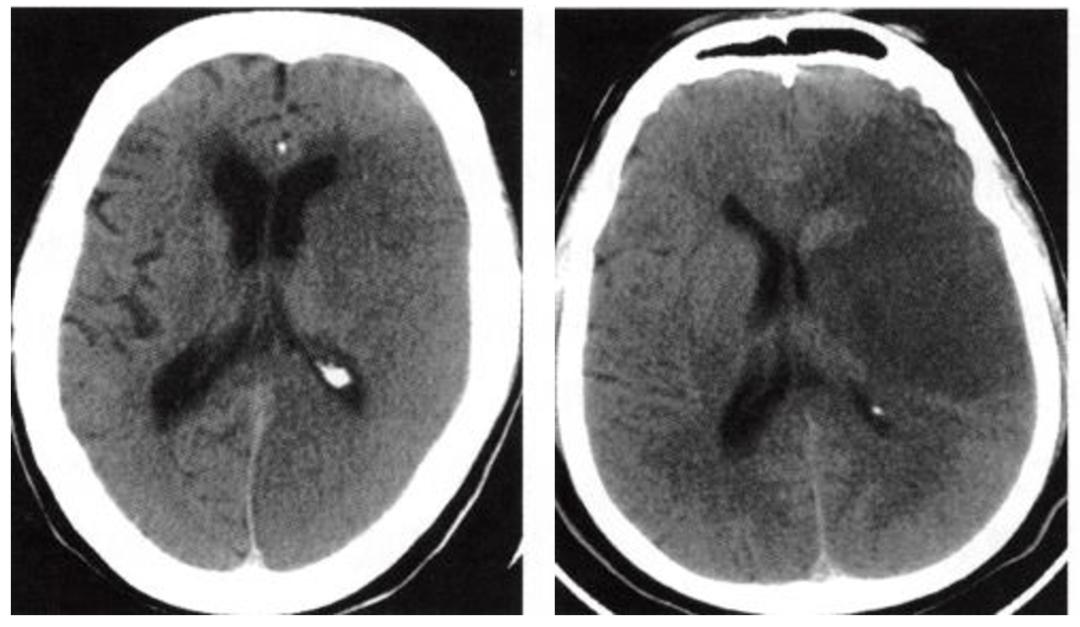

大面积脑梗死(large hemispheric infarction,LHI)与脑梗死有共同的发病原因与发展过程,是一种特殊类型的脑梗死,较一般病情要重,比较凶险,有典型的临床症状。主要是脑动脉主干阻塞所致,CT呈现大片状低密度阴影,多为脑叶或跨脑叶分布,脑组织损害范围较大,临床上除表现脑梗塞的一般症状外,还伴有意识障碍及颅内压增高,常常因小脑幕切迹疝而死亡。因此大面积脑梗死也称恶性大脑中动脉梗死,是导致人类死亡或残疾的重要疾病。

大面积脑梗死多因颈内动脉远端或大脑中动脉主干闭塞所致,从影像学角度出发,常以梗死面积或体积大小进行定义。不同研究使用不同的影像观察时点以及不同的影像学改变范围作为界值,以发病6h内CT显示低密度区>1/3或1/2大脑中动脉供血区或弥散加权成像(DWI)提示梗死体积>80ml较为常用,或梗死范围超过33%的大脑中动脉区域或ASPECTS<6的患者。